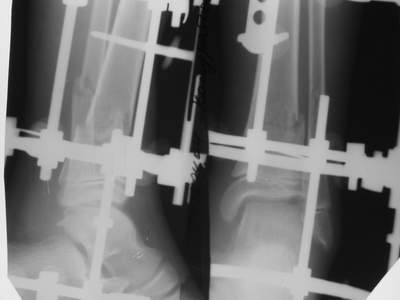

Уважаемые коллеги!Поступила пациентка 40лет, псевдоартроз Н/3 большеберцовой кости, оперирована 1,5-а года назад по поводу перелома ПИЛОНА в Австрии, травма горнолыжная.

после остеосиннтеза |  05.07.04 |  12.04.05 | Пластина удалена через 4-е месяца (миграция винтов), полимерная повязка на 2-а мес. Беспокоит деформация голени,укорочение 1-1,5см, боли незначительные, движения в г/стопном суставе в полном объёме, ходит с полной нагрузкой на ногу, подвижность в переломе не определяется. Одномоментное исправление деформации, костная пластика (chronOS)+ пластина? Аппаратная коррекция, затем пластина? Аппарат? Прошу Ваших советов. С Уважением А.Миронов